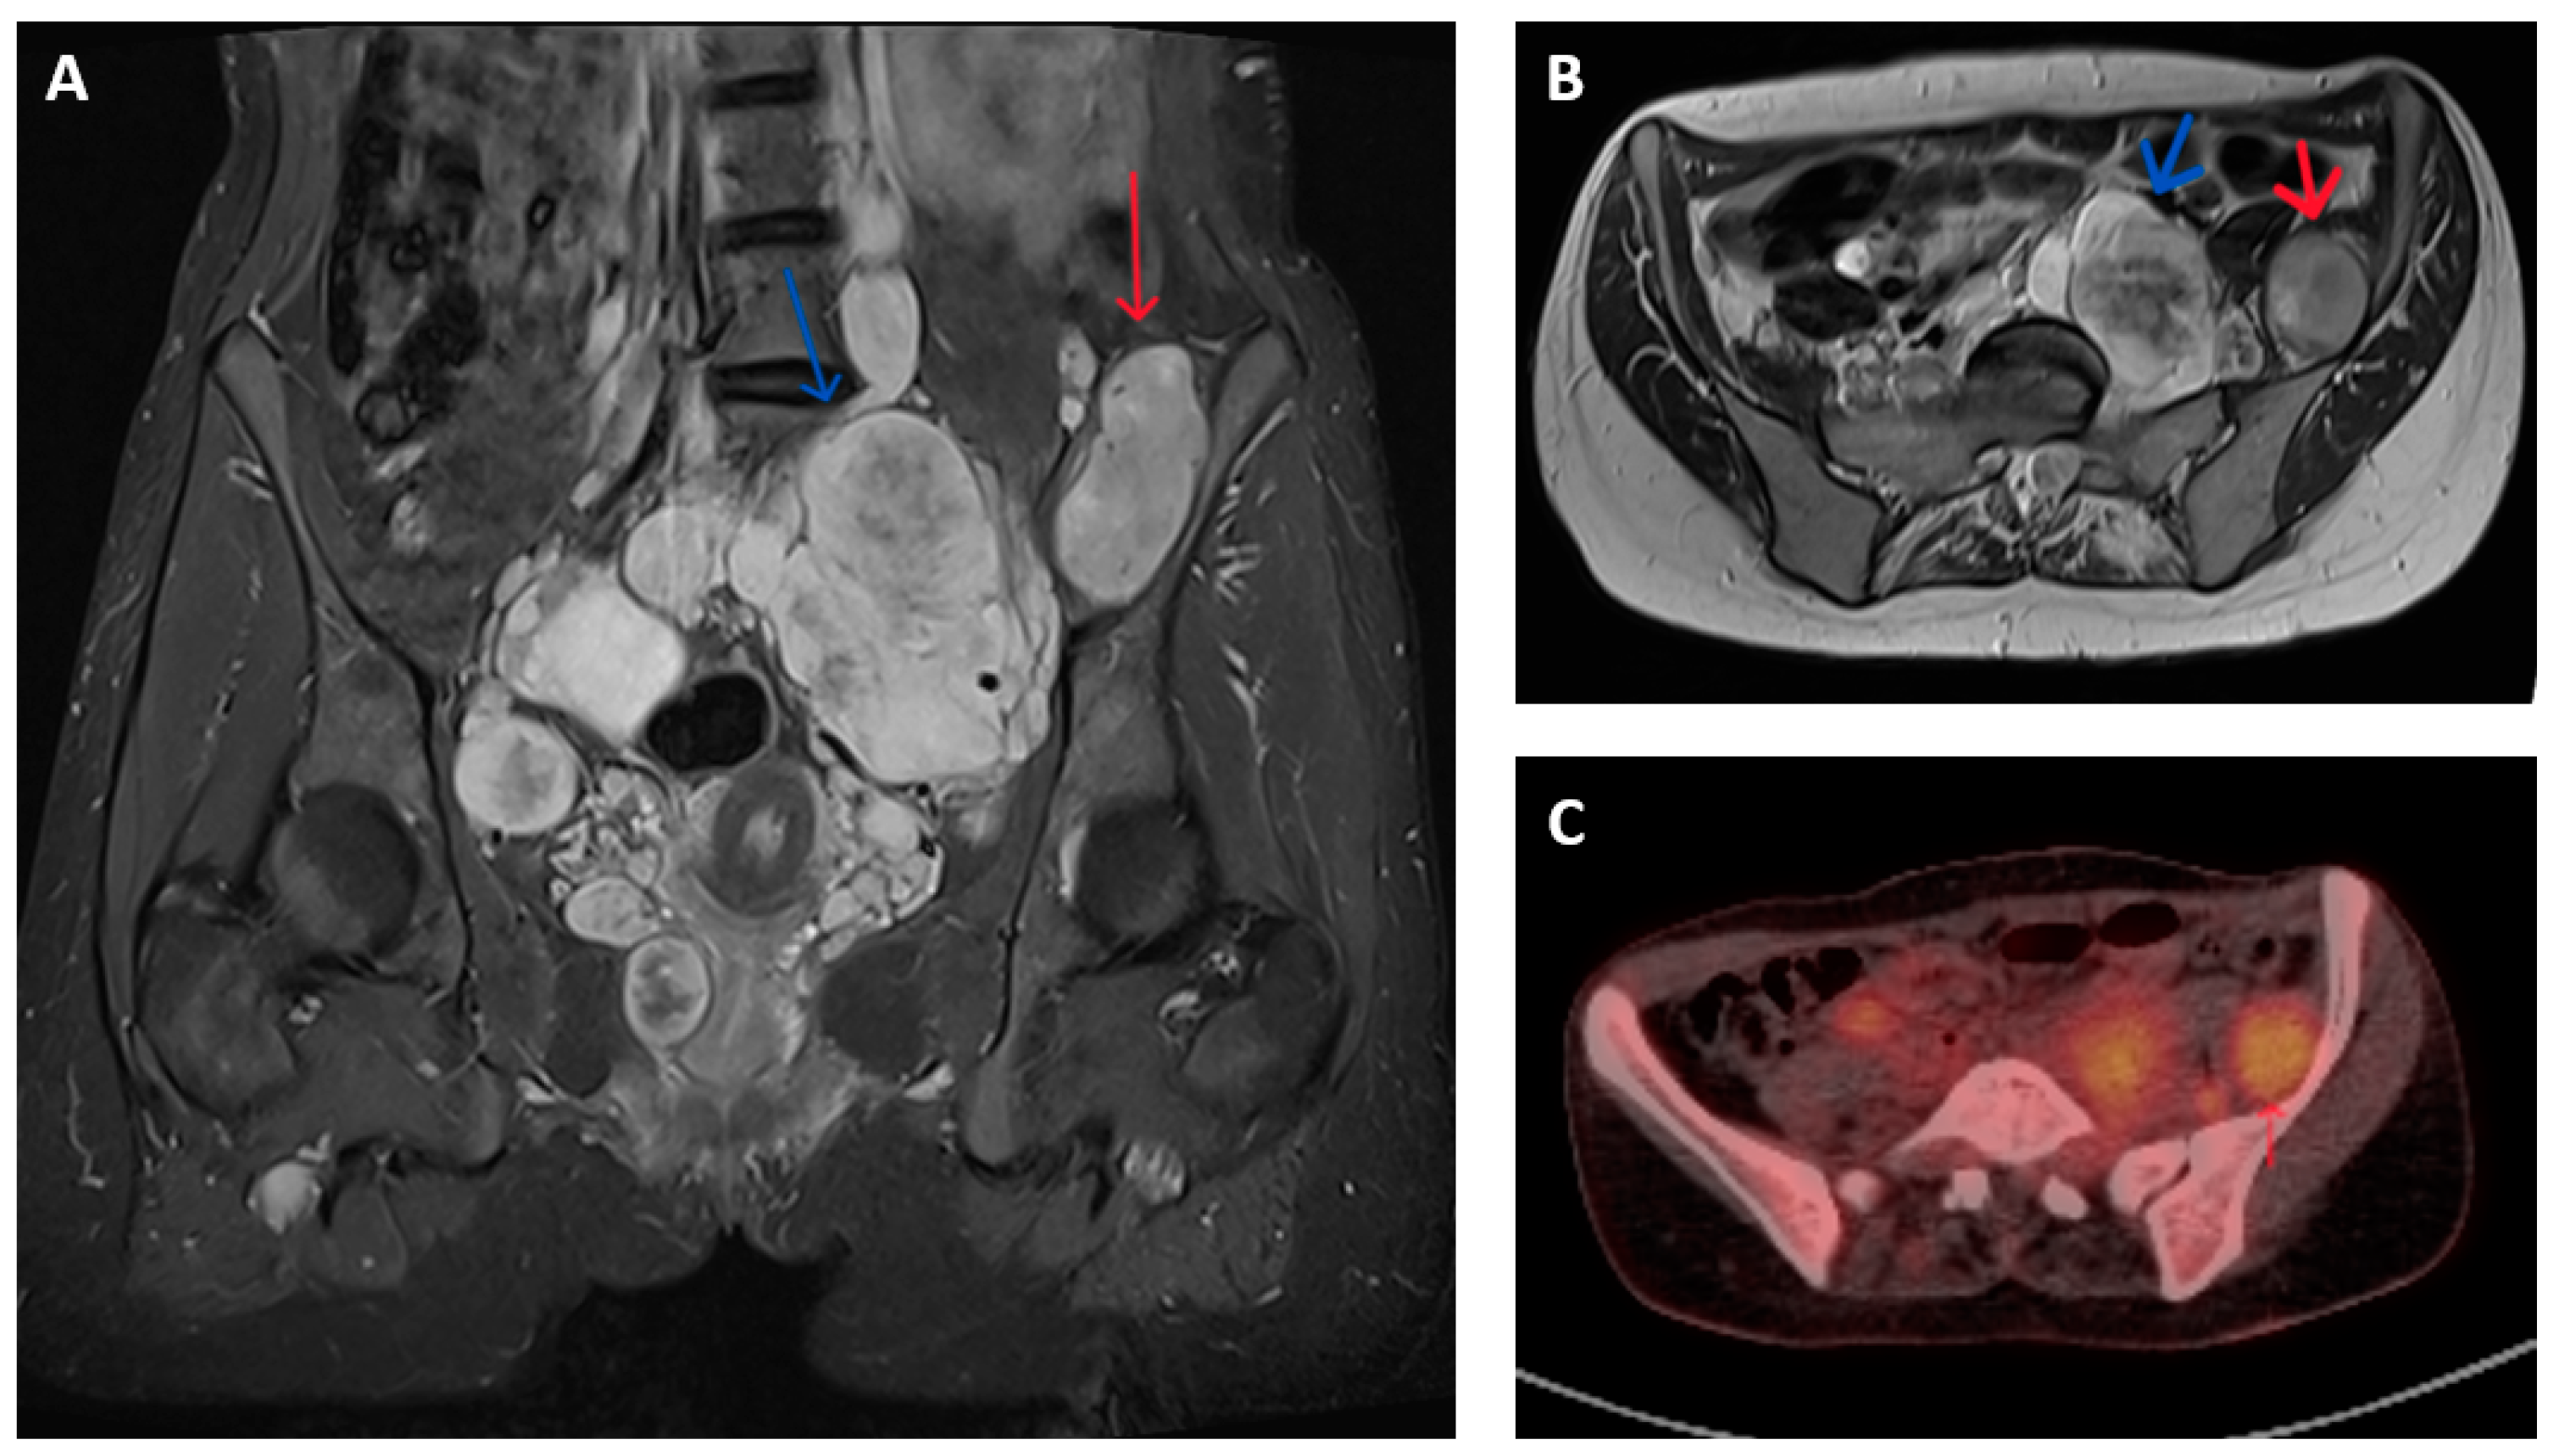

Imagining studies are essential to characterize the tumour extent and to differentiate between MPNST and benign nerve sheath neoplasms. Magnetic resonance imaging (MRI) is generally the preferred modality for assessment of the primary lesion, where features potentially indicative of malignancy include lesion size >5 cm, surrounding peritumoral oedema, intra-tumoral heterogenous enhancement on T1-T2 weighted images and irregular and/or invasive margins (Figure 1A,B) [11,12,13,14,15].

Figure 1.

Imaging appearances of benign and malignant nerve sheath tumours in patients with NF1. T2 weighted Short Tau Inversion Recovery (STIR) sequences in (A) coronal and (B) axial planes show numerous pelvic neurofibromata (blue arrows) and a lesion adjacent to left iliac bone that had shown significant growth compared to previous imaging (red arrow). This lesion showed features of atypia but no overt malignancy on biopsy but, on subsequent resection, was confirmed as containing high-grade MPNST. (C) Axial FDG-PET-CT image of corresponding region of same patient shows higher grade FDG uptake (SUV max 5.7) in malignant lesion (red arrow) compared to nearby non-malignant nerve sheath tumours.

MPNSTs typically have increased metabolic activity compared to benign neurofibroma. The use of fluorodeoxyglucose (18F-FDG) positron emission tomography (PET) provides additional means of distinguishing between malignant and non-malignant nerve sheath tumours. FDG-PET-CT is reported to have a sensitivity and specificity of over 90% for diagnosing MPNST in patients with symptomatic lesions, often by applying a cut-off in maximum standardized uptake value (SUV max) between 3 and 4 (Figure 1C). These results are variably limited by factors that include (a) dichotomization between malignant and non-malignant lesions that fails to account for the gradation of malignant progression, (b) a change in the histological classification of benign, atypical and malignant nerve sheath tumours subsequent to the majority of reported studies, (c) inclusion of a few atypical neurofibromas (and thus provide limited information in the use of FDG-PET to identify premalignant disease) and (d) inconsistency in criteria used to define PET positive or negative lesions [16,17,18,19].